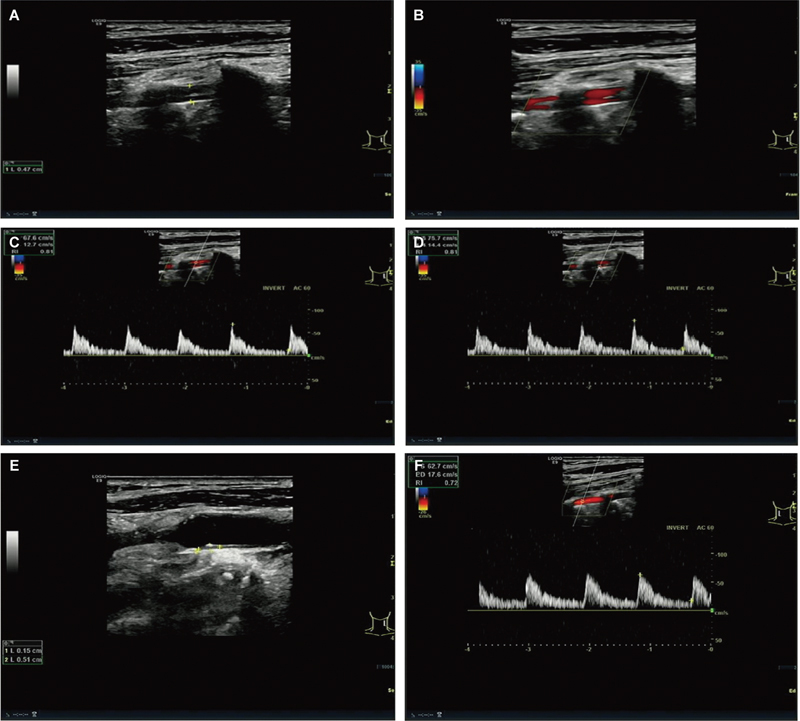

Case description: This article reports a case of an 82-year-old male patient who was diagnosed with VAF following a neck vessel ultrasound examination prompted by poor blood sugar control. The ultrasound revealed an abnormal course of the left vertebral artery, leading to the diagnosis of VAF.

Conclusion: Ultrasound, with its noninvasive nature and real-time imaging capabilities, is a valuable initial screening tool for diagnosing VAF. Despite its limitations, its ability to identify vascular anomalies such as VAF highlights its critical role in early detection, potentially improving patient outcomes and guiding clinical decision-making.